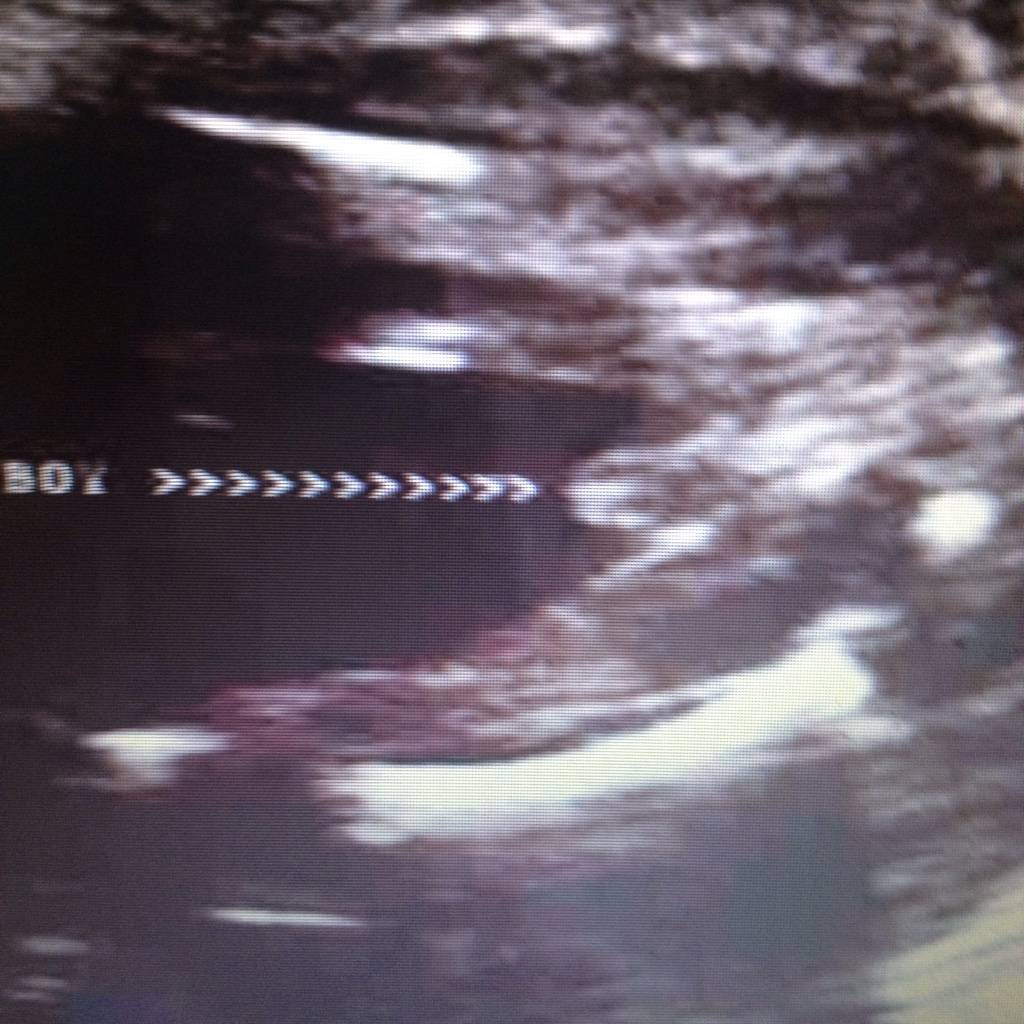

Witam w 19 tygodniu ciąży dowiedziałam się ze będę miała dziewczynkę w 20 tyg okazało się jednak , że to chłopak. Sama już nie wiem bo na jednym usg widać na pewno dziewuche a na drugim chłopca. Może to pempowina ?? Może ktoś mi pomoże rozwiązać ta zagadkę

Załączniki

• 4A8F5FF1-76CA-4DE0-AC12-5EDF08E820F2.jpg

4A8F5FF1-76CA-4DE0-AC12-5EDF08E820F2.jpg

596,4 KB · Wyświetleń: 23 651